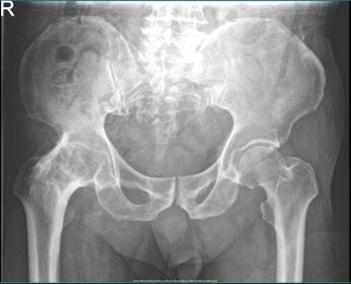

术后X光可以看到右髋关节恢复了正常的解剖位置及功能

由于充分的术前准备工作,术中配合良好,手术创伤及出血非常小。在骨科护理及康复团队快速康复规范化流程的指导下,患者至出院前已经能下床站立及行走,髋关节活动功能明显改善,对于手术效果非常满意。